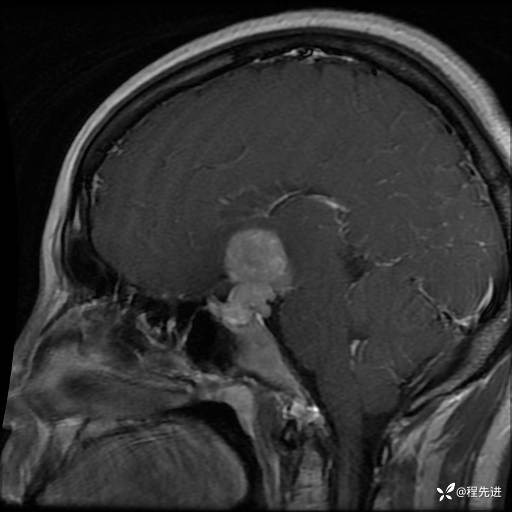

MRI平扫+增强:

T1+C: